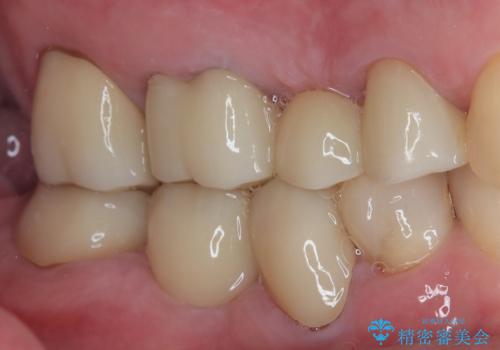

- 左下の4番目のセラミックの詰め物(セラミックインレー)が欠けたとのことで来院された患者様です。以前にセラミックの詰め物の治療を行い、噛み合わせが強く割れてしまっていました。今回はセラミックの詰め物のやり替えだとまた欠けてしまう可能性があるのでフルジルコニアクラウンでの治療を行うことにしました。拡大鏡視野下でセラミックの詰め物、虫歯を除去しフルジルコニアクラウンに適した形に整えました。

歯と歯茎の間に圧排糸と呼ばれる糸を入れてシリコーン印象を行いました。

見た目、機能面ともに満足していただけました。

噛み合わせが強い方なので今後はセラミックが割れないようにナイトガードを使っていただきながら、定期的にクリーニングで通ってもらう予定です。